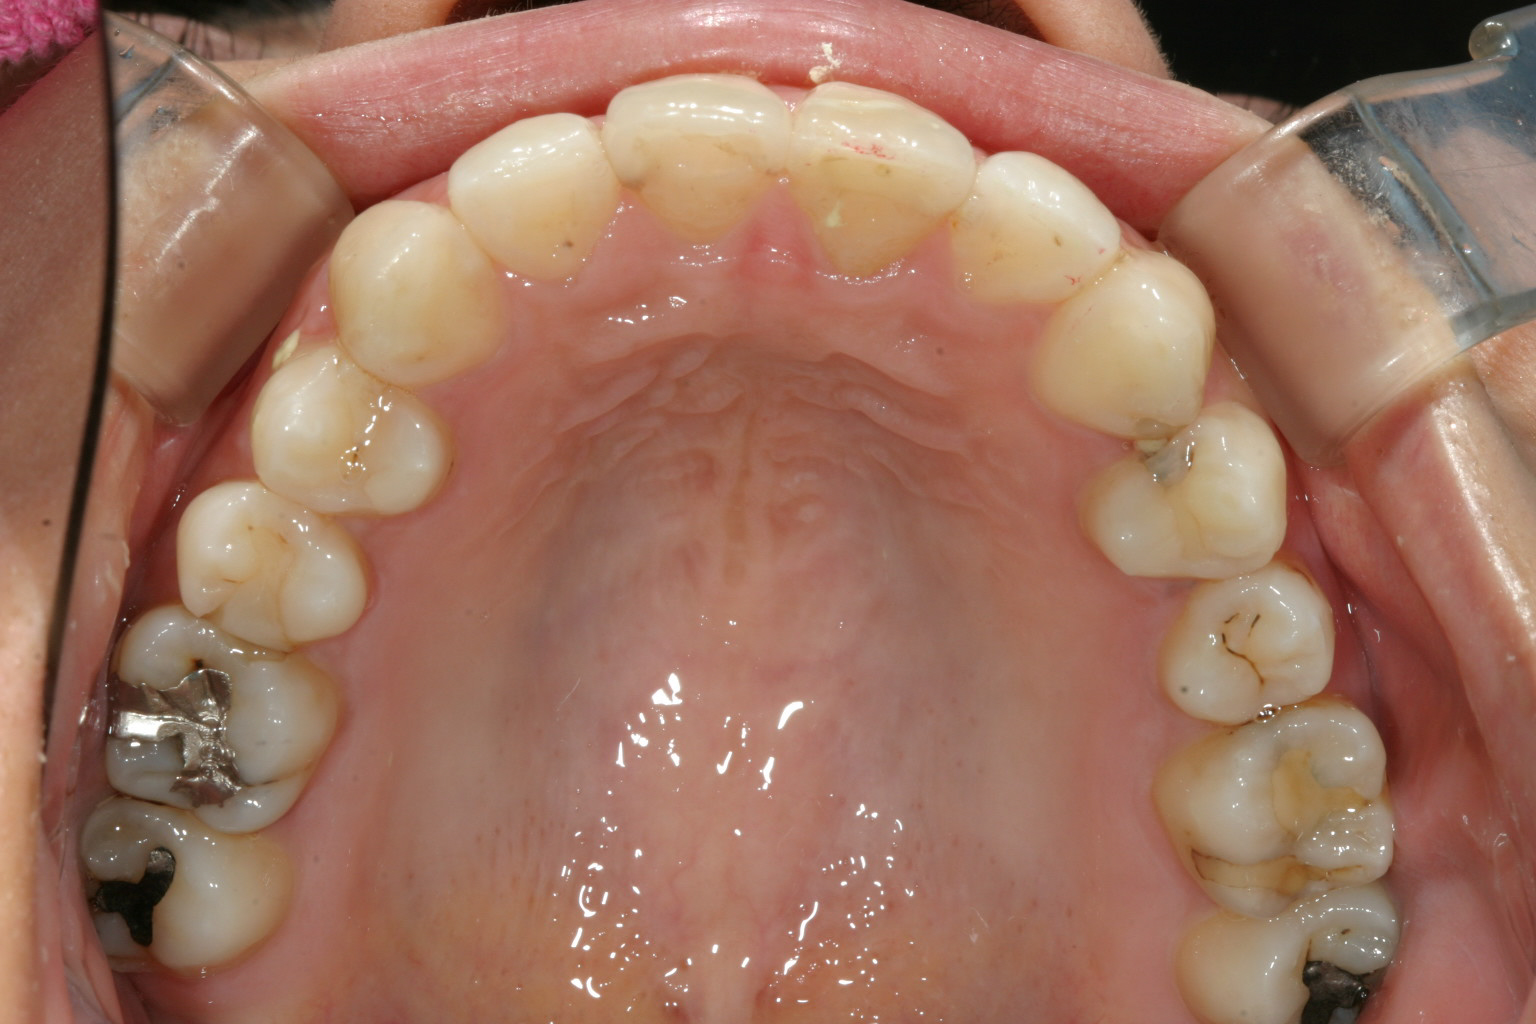

前歯も左側小臼歯も綺麗に回転戻しました。

下顎も綺麗に改善されています。

今回の症例は前歯の歪みと挺出の改善と左側小臼歯の回転戻しです。

ここで一番難しいのは小臼歯の回転です。

インビザラインではなかなか回転させるのは難しくラビアルサイドにマルチループを使用する事により回転させました。